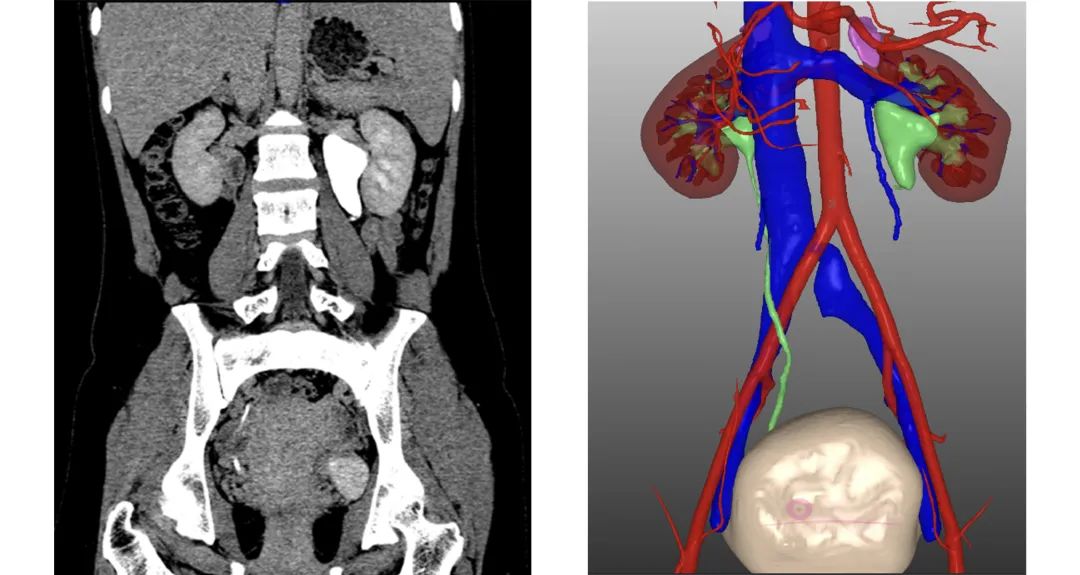

接受手术的患者,女,29岁,主诉左侧间断腰痛5个月。泌尿系超声提示左肾中度扩张积水,考虑左侧肾盂输尿管连接部狭窄;尿路造影提示:左侧输尿管上段局部管壁增厚、管腔折叠,继发左肾积水。为保证手术的顺利进行,术前采用三维数字医学影像技术平台对狭窄的部位、血管、脏器等进行三维重建,可视化评估梗阻病变的部位及周围的血供情况。李学松院长及团队结合患者的病情对手术方案进行讨论分析,最终决定使用单孔手术系统进行经脐经肠系膜入路左侧输尿管息肉切除输尿管吻合术。